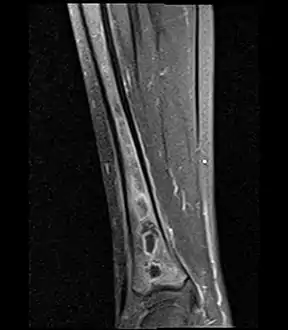

Fat saturated STIR (short tau inversion recovery) image showing hyperintense edema in the calf musculature, marrow edema, and subperiosteal pus. The intramedullary abscess cavity is hyperintense as well.